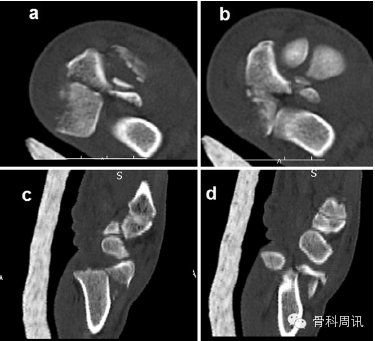

一名35歲男性從大約5米的高處墜落後,摔傷其右上肢,送往我院急診室就診。體格檢查顯示腕部銀叉樣畸形,所有手指無法正常屈伸,並且第一、二、三根手指均出現感覺喪失。橈動脈搏動不明顯。X光片顯示橈骨遠端骨折伴腕骨從尺骨遠端背側脫位(圖1)。在麻醉狀態下嚐試采取閉合複位術。複位失敗後,進行CT掃描檢查。CT顯示,橈骨莖突骨折和橈骨遠端粉碎性骨折伴腕骨背側移位和腕骨近端骨折移位。下尺橈關節顯示穩定(圖2)。由於複位失敗,所以采取手術治療。

Fig. 2. Axial (a and b) and sagittal(c and d) CT images showing dorsally and proximally displaced radiocarpal fracture dislocation.

圖2 顯示背側和近端移位的橈腕關節骨折脫位的軸向(a and b)和矢狀(c and d) CT圖像。